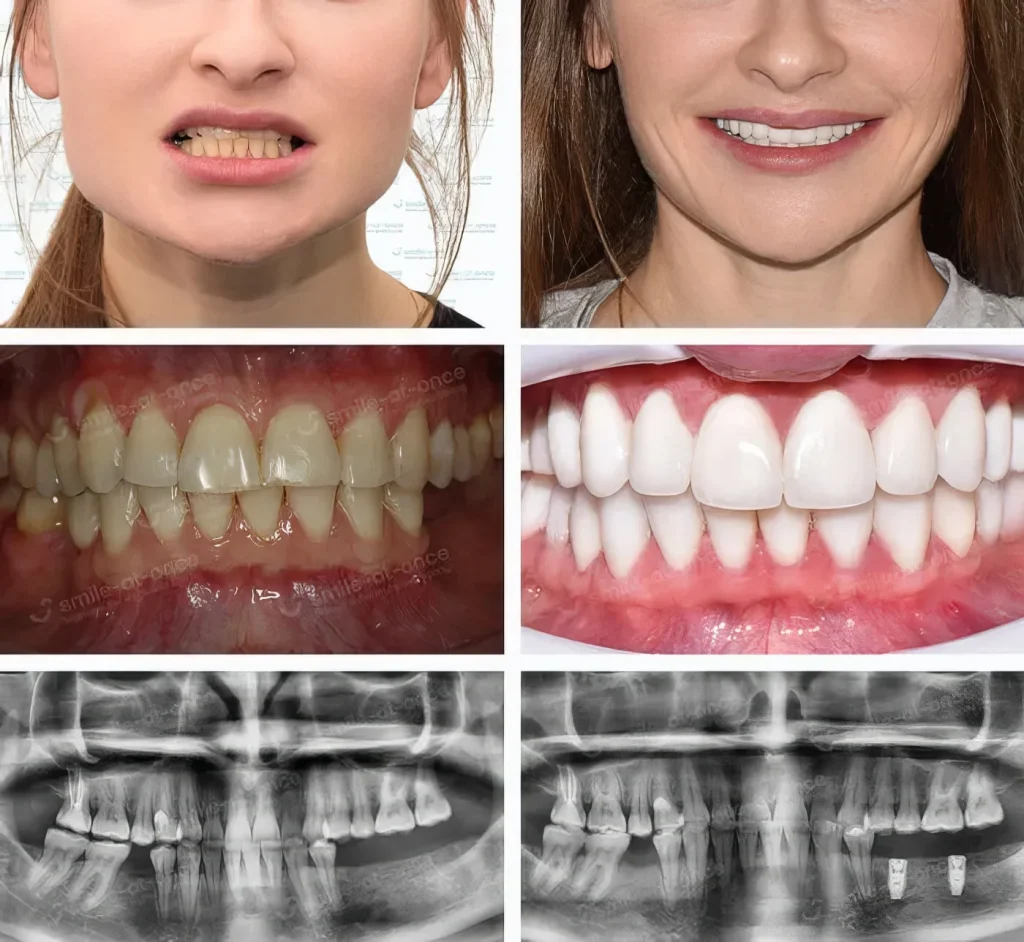

Мы провели комплексное лечение: сначала — лазерный кюретаж и антибиотики, потом — курс комплексной терапии для восстановления кости и десны, и только после этого — установка имплантов.

Через три дня она сказала: «Я наконец-то могу говорить, не прикрывая рот ладонью». А потом — просто улыбнулась.

Это и есть результат. Не техника. Это — возвращенная гордость. Имплантация зубов невозможна без здоровья десен — и именно поэтому мы лечим не зубы, а причину. Потому что если десны больны — даже самый идеальный имплант не приживётся. Мы восстанавливаем зубочелюстную систему в комплексе.